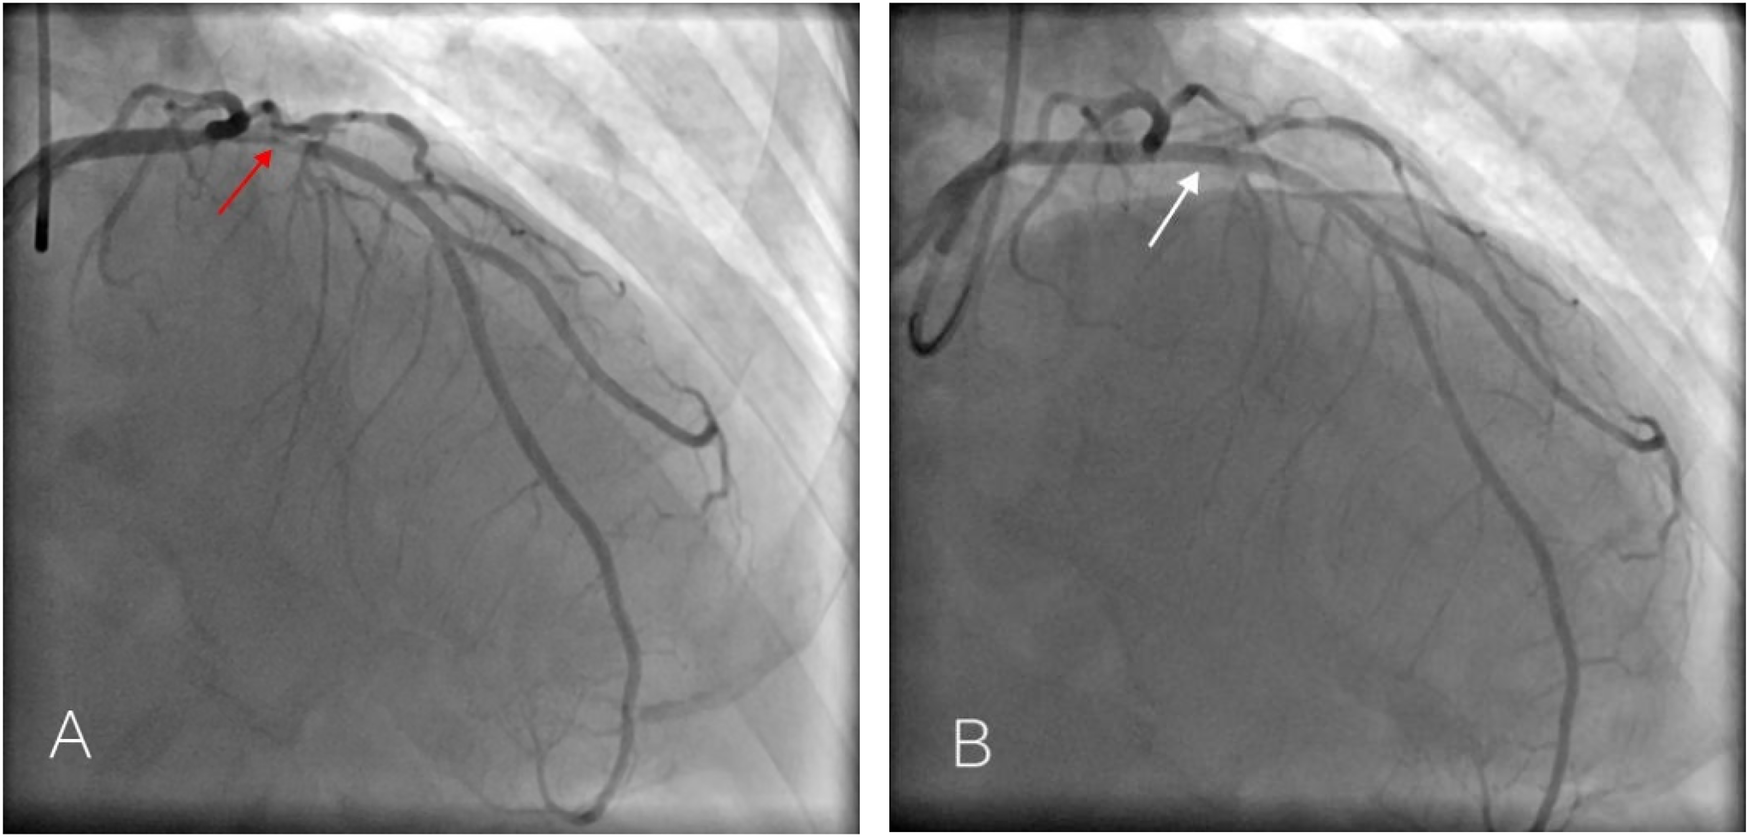

Multiple rechecks of ECG showed a dynamic evolution of the ST-segment, which is gradually rising. In our hospital, emergent coronary angiography demonstrated 75%–90% stenosis in the proximal and middle segments of the LAD (Figures 2A,B). One stent was implanted, and the blood flow was restored to TIMI III (Figure 2C). Five hours after the initial ECG, QS complexes were observed on the follow-up ECG in leads V1–V6, with ST-segment elevation of 0.1–0.9 mV in leads II, III, aVL, and V2–V6, accompanied by upright T waves in leads V2–V6, consistent with a typical acute extensive anterior wall myocardial infarction (Figure 3). Ultrasensitive troponin T (TNT) was 10.0 µg/L, creatinine kinase (CK) was 5,382.4 U/L, CK-MB was 485.3 U/L, and D-dimer was 0.74 µg/mL. On the third day after percutaneous coronary intervention (PCI), the ECG showed that the ST-segment gradually decreased to the isoelectric baseline level, and pathological Q waves still existed in leads V1–V5, with inverted T waves (Figure 4). Echocardiography showed left heart enlargement, weakened motion of the anteroseptal segments, anterior wall, and apex, mild pulmonary hypertension, and a small amount of pericardial effusion. The patient had impaired left ventricular systolic and diastolic functions with left ventricular ejection fractions (LVEF) 35% and E′/A′ = 0.71. The patient received dual-antiplatelet therapy (aspirin 100 mg/day and ticagrelor 90 mg/12 h), and chest pain was relieved. The patient’s chest pain symptoms were significantly relieved, and he was discharged on the 14th day after PCI.

Figure 2

Emergency coronary angiography of Case 1 patient showed 75%–90% stenosis in the proximal LAD [(A,B) red arrow] and was successfully recanalized after stent implantation. [(C) white arrow].